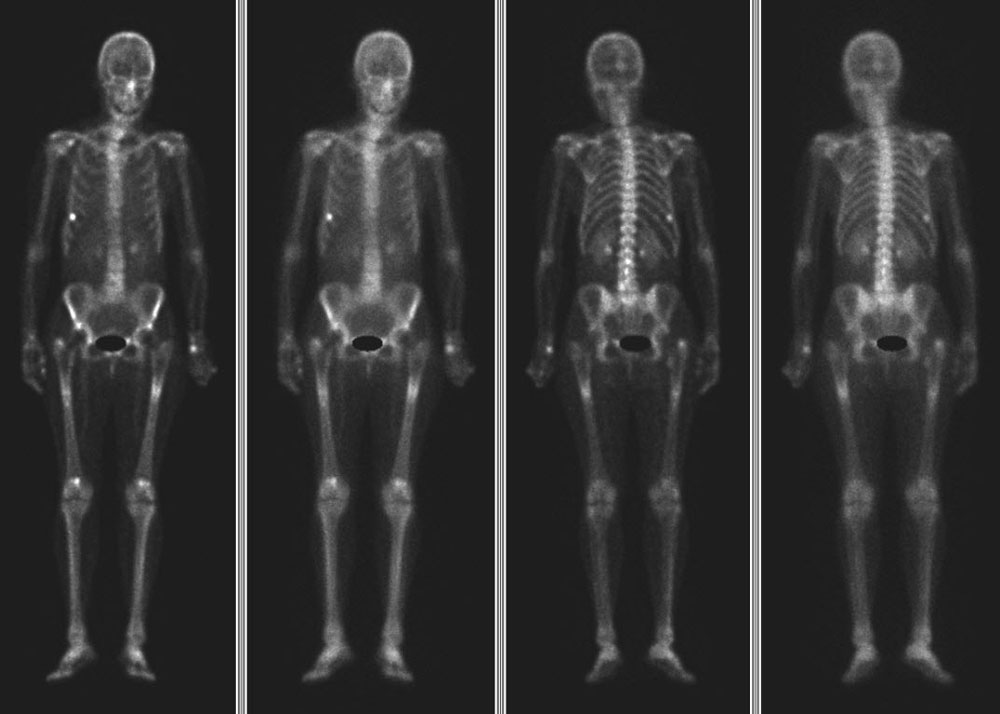

Knochenszintigraphie

Bei der Knochenszintigraphie spritzen wir dem Patienten ein kurz wirksames, schwach radioaktives Medikament. Das Medikament lagert sich vornehmlich dort ein, wo ein gesteigerter Knochenstoffwechsel vorliegt. Mittels spezieller Detektoren, den sogenannten Gamma Kameras, lässt sich die Aktivität der Knocheneinlagerung dokumentieren.

- Knochen Szinthigaphie Anreicherung Hüftporthesen